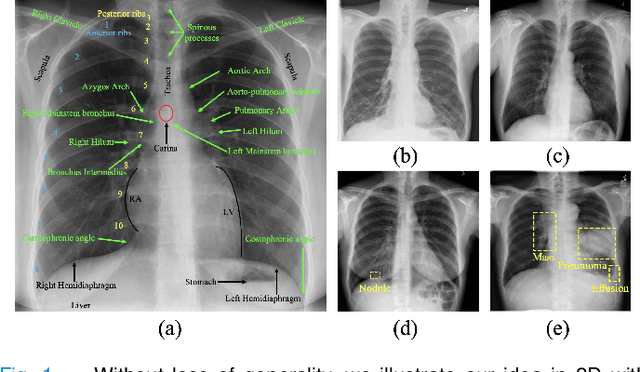

Abstract:Foundation models have been successful in natural language processing and computer vision because they are capable of capturing the underlying structures (foundation) of natural languages. However, in medical imaging, the key foundation lies in human anatomy, as these images directly represent the internal structures of the body, reflecting the consistency, coherence, and hierarchy of human anatomy. Yet, existing self-supervised learning (SSL) methods often overlook these perspectives, limiting their ability to effectively learn anatomical features. To overcome the limitation, we built Lamps (learning anatomy from multiple perspectives via self-supervision) pre-trained on large-scale chest radiographs by harmoniously utilizing the consistency, coherence, and hierarchy of human anatomy as the supervision signal. Extensive experiments across 10 datasets evaluated through fine-tuning and emergent property analysis demonstrate Lamps' superior robustness, transferability, and clinical potential when compared to 10 baseline models. By learning from multiple perspectives, Lamps presents a unique opportunity for foundation models to develop meaningful, robust representations that are aligned with the structure of human anatomy.